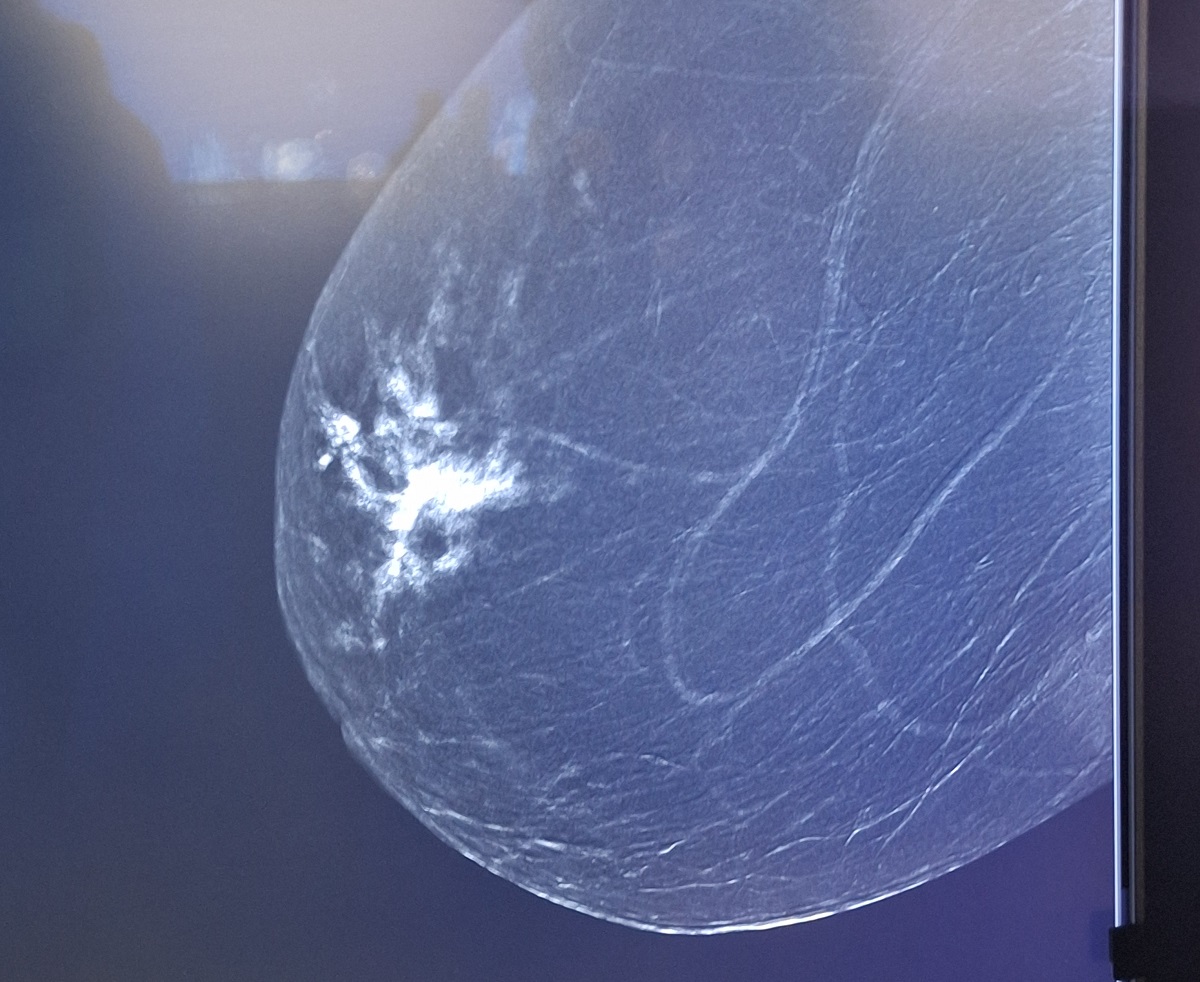

Radioloģe dr. Marta Krūmiņa skaidro, ka šis izmeklējums sniedz iespēju precīzāk noteikt patoloģiskas izmaiņas krūts audos: “Izmeklējuma laikā pacientei caur katetru vēnā tiek ievadīta kontrastviela. Pēc tam asistents ar mamogrāfijas iekārtas palīdzību noteiktā laika intervālā uzņem mamogrāfijas attēlus. Savukārt ar speciālas datorprogrammas palīdzību tiek iegūti kontrastmamogrāfijas attēli, kuros redzamas zonas, kur notiek pastiprināta asinsrite – tās bieži vien norāda uz patoloģiskām izmaiņām. Tas mums ļauj labāk saprast veidojumu izmēru, apjomu un raksturu.”

Ārste M. Krūmiņa skaidro, ka līdz šim veiktajos mamogrāfijas izmeklējumos iespējams detalizēti redzēt visu krūts uzbūvi – dziedzeraudus un struktūru –, savukārt kontrastmamogrāfija izceļ tikai tās vietas, kurās ir izmaiņas šūnu līmenī. Šādā veidā radiologi var precīzāk noteikt iespējamās patoloģijas, arī gadījumos, kad citi izmeklējumi – sonogrāfija vai parastā mamogrāfija – nav devuši skaidru rezultātu.

“Kontrastmamogrāfija ļauj mums atrast arī tās izmaiņas, kas iepriekš paliktu nepamanītas. Tā palīdz gan slimības agrīnā diagnostikā, gan ārstēšanas efektivitātes izvērtēšanā,” uzsver dr. M. Krūmiņa.